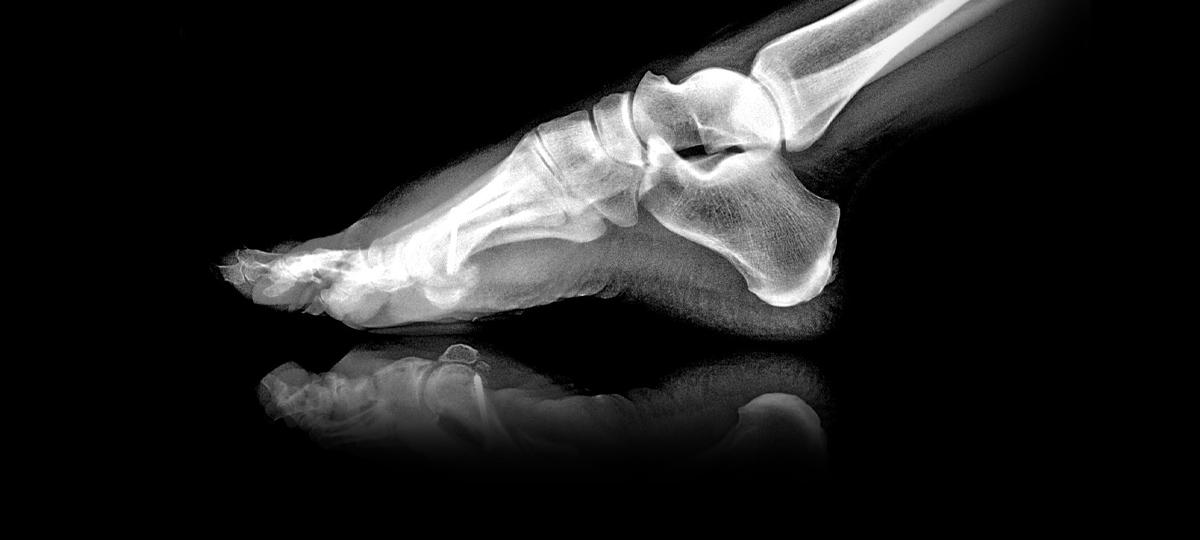

Во время гололеда я упала на тротуаре у своего дома, поскольку дорожка не была посыпана песком. В результате падения получила закрытый перелом голени. Могу ли я предъявить к ЖСПК претензии материального характера в связи с полученной травмой? (Елена, Брест)